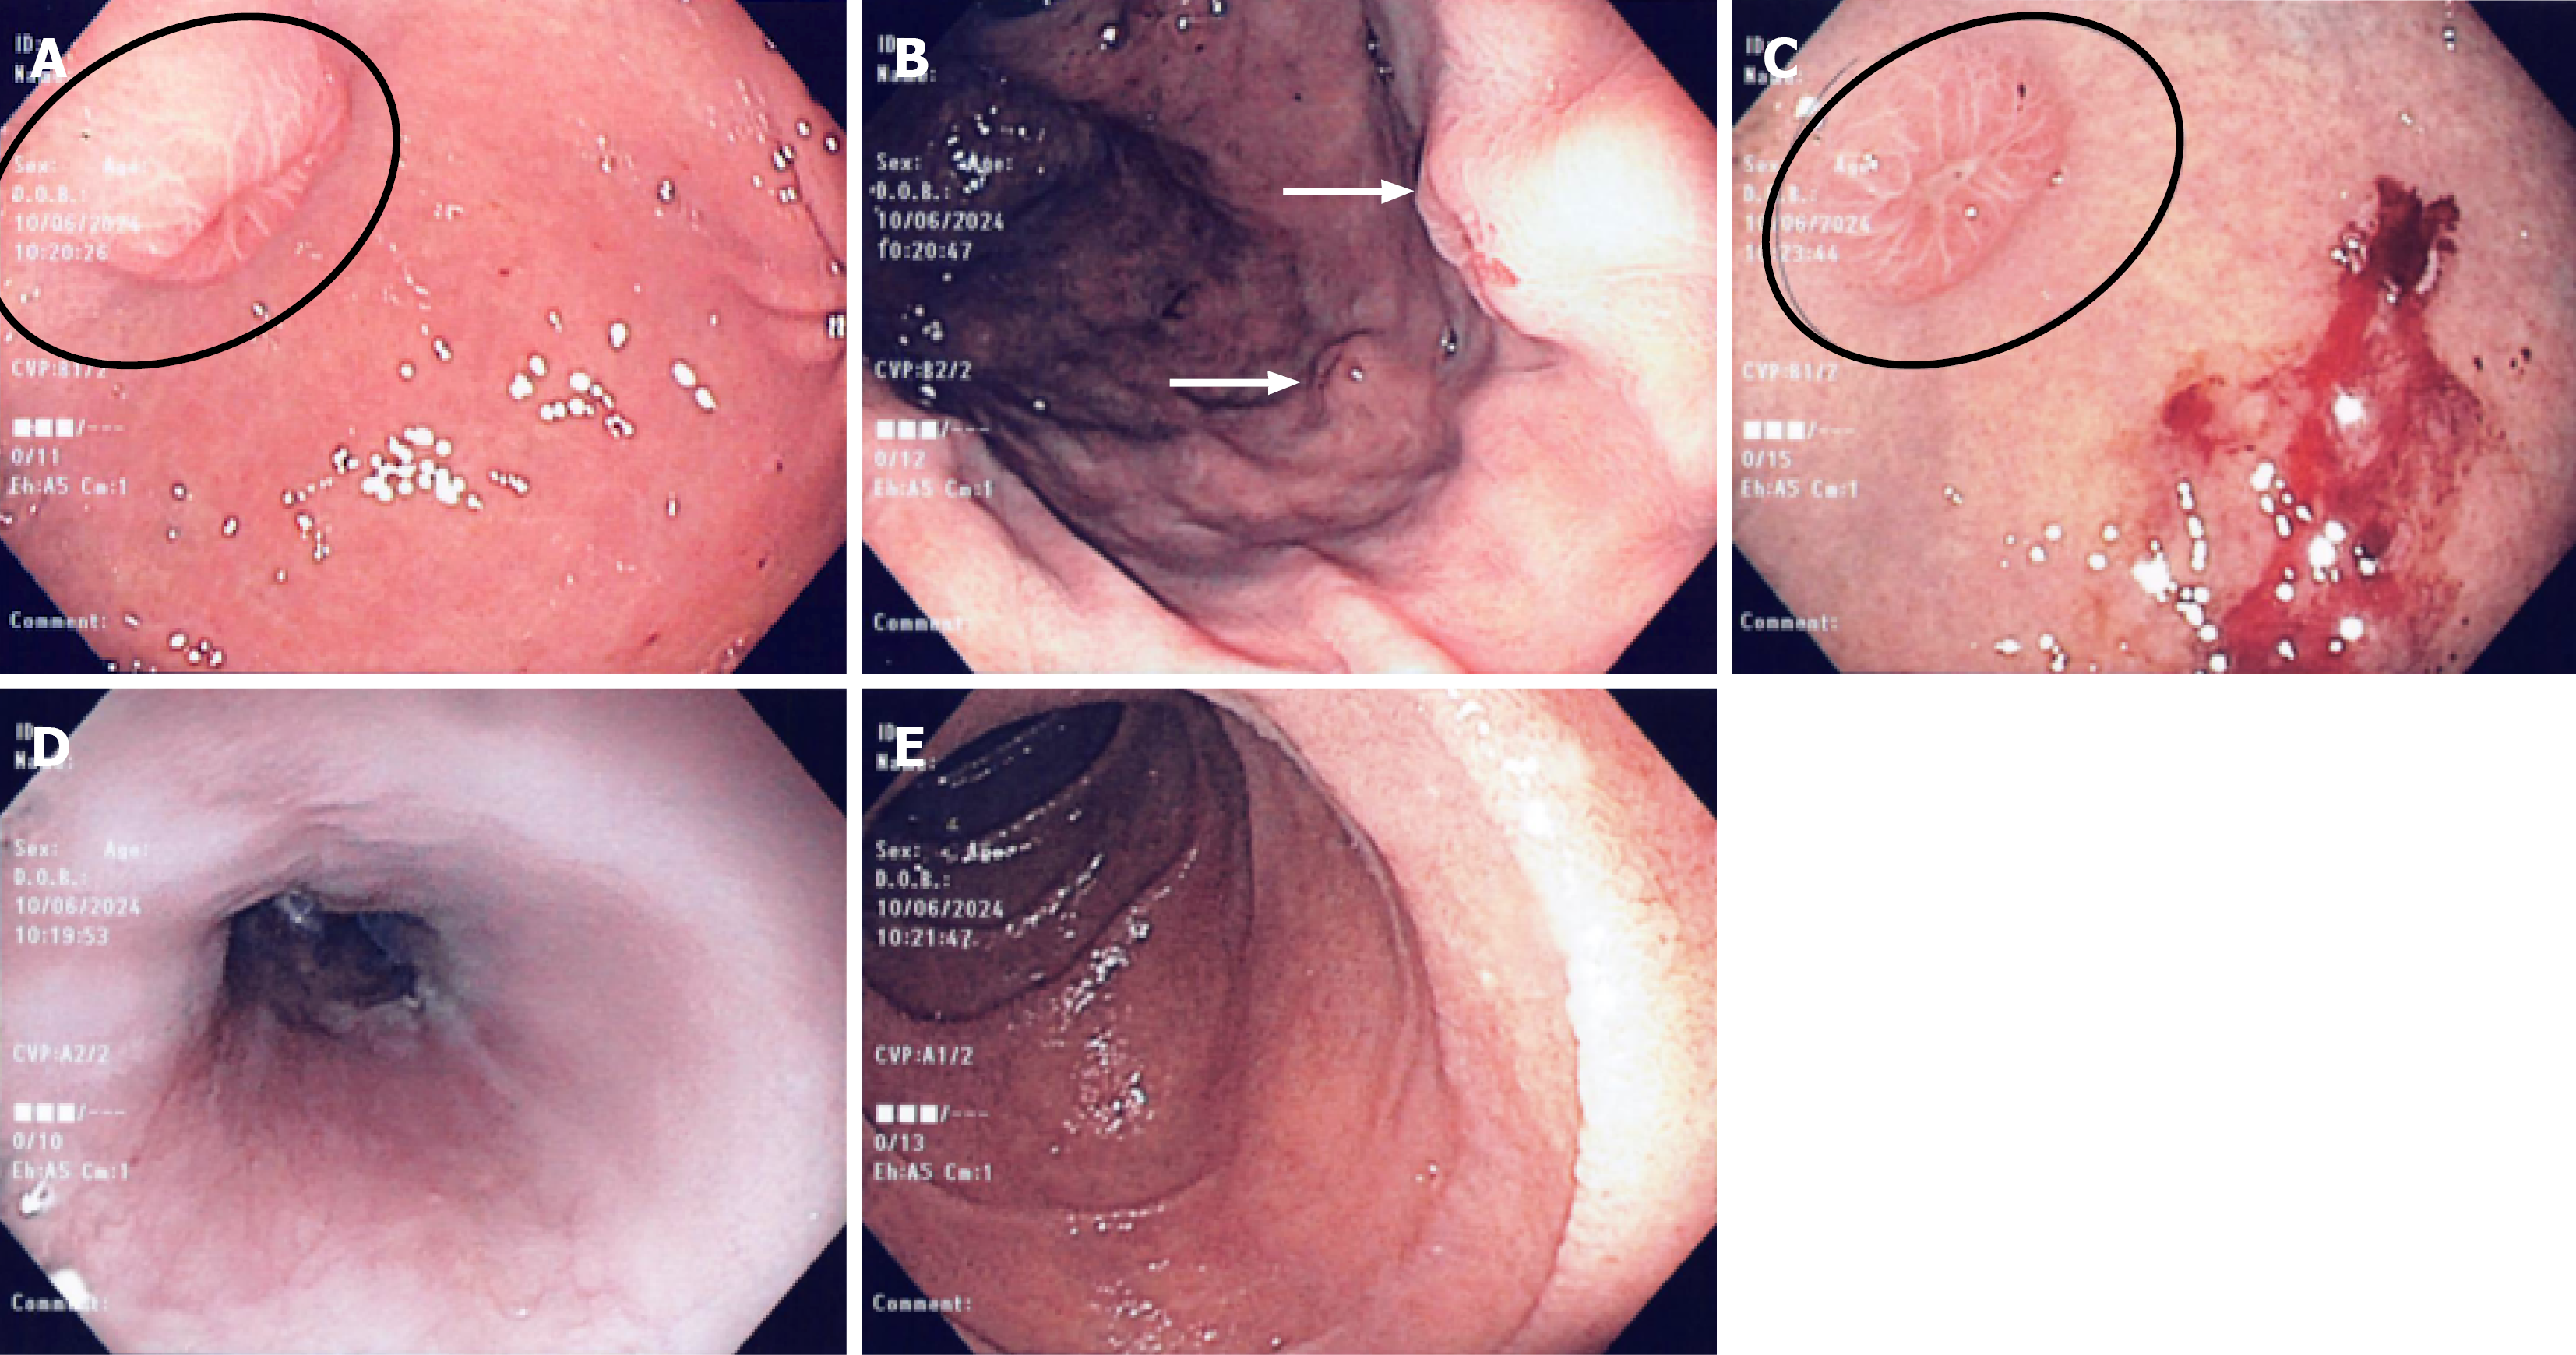

Figure 2 Gastroscopy.

A: Gastroscopy revealing well defined subepithelial nodule in the gastric antrum with a central umbilicated depression (black circle); B: Two subepithelial nodules (white arrows) observed on retroflexion in the gastric body; C: Central umbilication seen in the circled nodule (black circle). Post biopsy heme evident on the adjacent nodule to the right; D: Normal esophagus; E: Normal duodenum.